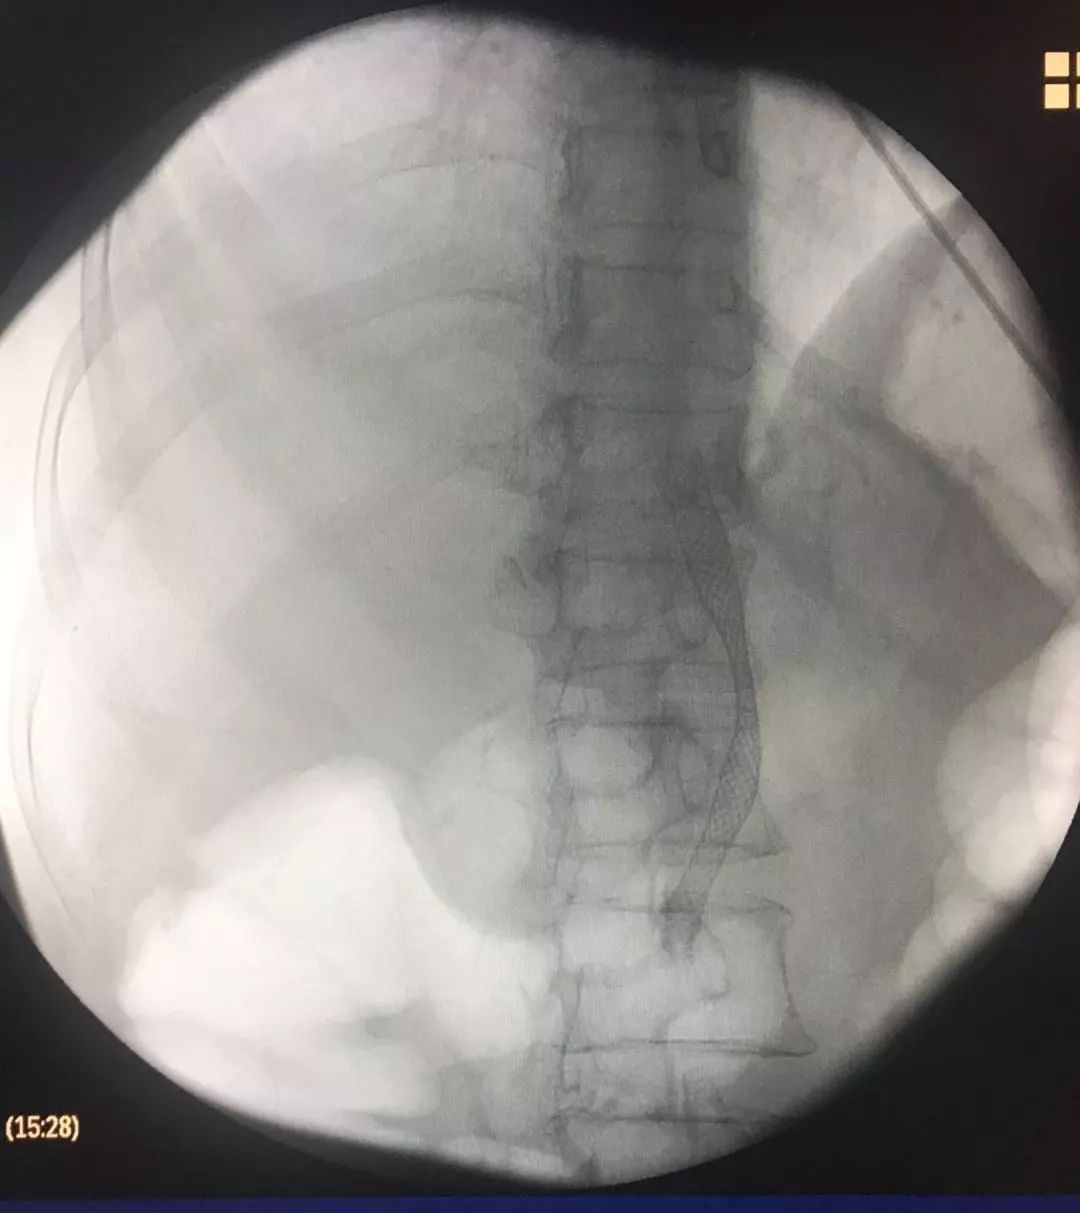

患者的影像结果显示,心脏位于右侧

CT提示:全内脏反位

CT提示:胆囊癌伴肝内多发转移

造影示:胆总管上段梗阻